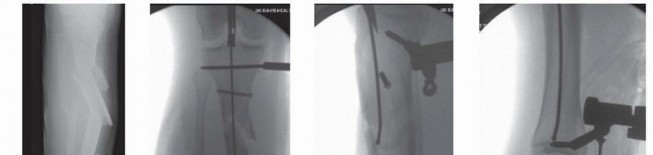

### FIG 1 • A. The metaphyseal segment extends with knee flexion secondary to the pull of the patellar tendon. B. The anterior tibial crest is palpable and represents the vertical lateral border of the tibia. Palpation of the crest can help aid in starting wire orientation. C. Anterior neurovascular structures are at risk during anterior placement of distal interlocking bolts; internal rotation may decrease the risk of arterial injury. A detailed neurovascular examination is critical to avoid the devastating complications associated with compartment syndrome, which can occur in both closed and open fractures (see Cha 53). ## IMAGING AND OTHER DIAGNOSTIC STUDIES Full-length anteroposterior (AP) and lateral plain radiographs are necessary to adequately evaluate the tibia and fibula. Complete orthogonal views of the tibia and fibula help evaluate for concurrent fractures or dislocation and any preexisting deformity or implants. Orthogonal radiographic views of the knee and ankle are required to rule out articular involvement. Axial computed tomography (CT) scan can be used for proximal and distal fractures to rule out intra-articular fracture extension. Nondisplaced fracture lines are common. Gunshot wounds may merit CT evaluation to rule out intra-articular bullet fragments and intra-articular fracture extension. Magnetic resonance imaging (MRI) is not useful for most diaphyseal or metadiaphyseal fractures. Ankle-brachial index (systolic pressure in injured leg below injury divided by systolic pressure of the brachium) after fracture reduction should be used to rule out vascular injuries in severely displaced fractures or fractures with severe soft tissue injury. Values of less than 0.9 may be indicative of vascular injury, requiring further investigation. 18 549 Compartment pressure evaluation with a commercially available handheld single-stick monitor or with a sideported catheter connected to a pressure monitor (using the arterial line setup) is indicated in patients who have severe or increasing swelling and are not able to comply with physical examination and questioning. Observe for early signs of compartment syndrome in all patients with tibial diaphyseal fractures. Open fracture does not preclude development of compartment syndrome. Measure the pressure difference between the diastolic pressure and the intracompartmental pressure—a differential value of less than 30 mm Hg is considered an indication for a four-compartment fasciotomy. 17 ## NONOPERATIVE MANAGEMENT Nonoperative management is indicated in ambulatory patients for closed and open fractures that do not require flap coverage and that do not present with excessive initial shortening or unacceptable angulation when a cast is applied ( FIG 2). An intact fibula with an axially unstable fracture pattern (ie, short oblique, butterfly fragment, or comminuted) is at risk for shortening and varus deformities and is a relative contraindication to nonoperative management. A higher rate of malunion and nonunion with nonoperative management is seen in higher energy fractures. 2, 9 Joint stiffness, especially hindfoot, is common with all forms of prolonged immobilization. 7, 22 Initial treatment includes ˜2 weeks of a long-leg splint, then a long-leg cast for 2 to 4 weeks. When the initial swelling has subsided, the patient is graduated to a patellar tendon or functional brace. Weight bearing is allowed and encouraged.

### FIG 2 • A-C. An oblique diaphyseal tibial shaft fracture treated nonoperatively to union. (Courtesy of Paul Tornetta III, MD.) Radiographs are evaluated at 1- to 2-week intervals over the first month of treatment to confirm maintenance of acceptable alignment. ## SURGICAL MANAGEMENT